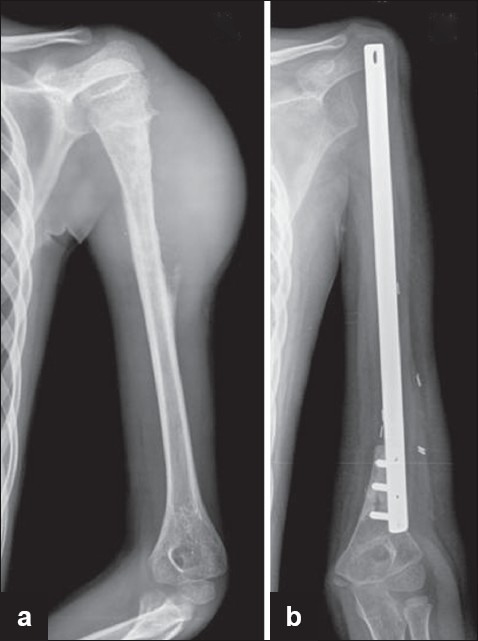

After the tumor is resected the plate is anchored to the distal bone stump with bicortical screws passed through the distal holes [Figure 2]. Polymethylmethacrylate bone cement is digitally packed into the medullary canal of the short distal stump to improve the quality of the screw hold. A commercially available polypropylene mesh (Prolene TM - Johnson and Johnson) is passed through the proximal hole and anchored circumferentially to the glenoid with the help of four to six sutures passed through bone, using No: 2 Ethibond Excel TM (Johnson and Johnson), a polyester braided nonabsorbable material. The mesh also serves as an anchor for any residual capsule or para-articular soft tissue. [2]  | Figure 2: (a) Radiograph showing Ewing's sarcoma of the proximal humerus (b) Radiograph showing reconstruction with the customised plate

Click here to view |